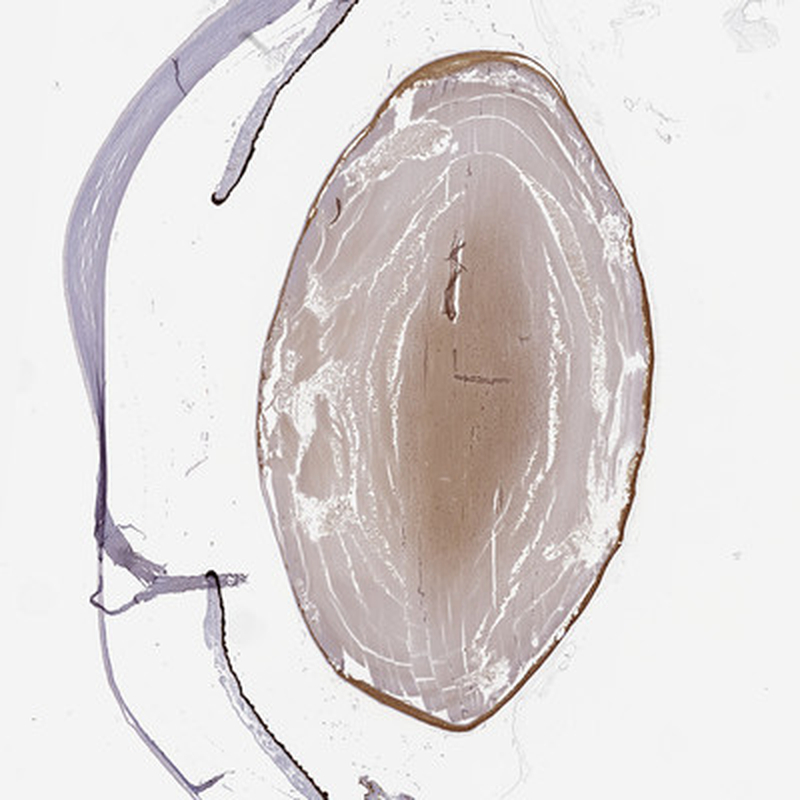

Immunohistochemical staining of human eye shows moderate positivity in lens